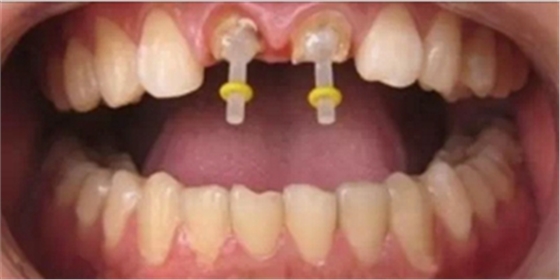

1、 正常情況下所有前牙的髓腔入口總在舌側(cè),最初的入鉆部位在舌面正中標(biāo)記“×”處(下圖)。通常的錯誤是開髓部位太靠齦端。

2、 最初入鉆時是以高速錐形的裂鉆或金剛砂鉆針在冷卻條件下,與舌面成直角操作(下圖),只需穿透牙釉質(zhì)層,不用加力,讓鉆自行切割就可以。